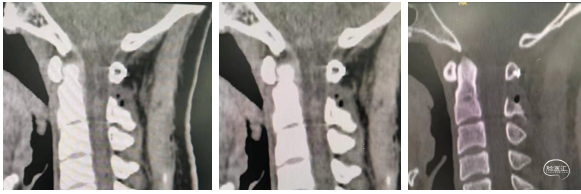

图6 术后3天复查MRI及CT:脊髓回位到正中,未见肿瘤残留,椎板骨质完整。